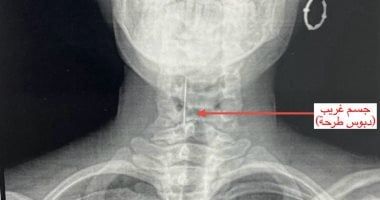

إجراء الفحوصات الطبية اللازمة للفتاة قبل الجراحةوتابعت المستشفى، أنه على الفور تم إجراء الفحوصات اللازمة والأشعة التي أكدت استقرار "الدبوس" في منطقة دقيقة بمدخل مجرى التنفس، مما شكل خطورة على حياتها.

جراحة ناجحة واستخراج الدبوس من الحنجرةوأوضحت، أنه تم تجهيز المريضة للجراحة تحت إشراف وتوجيه الدكتور سامر بديع، رئيس قسم الأنف والأذن والحنجرة، والدكتور إيهاب سعيد، رئيس قسم التخدير، حيث تم تجهيز المريضة للعمليات فورا، حيث ضم الفريق الطبي كلاً من الدكتور عبد الرحمن الباهي مدرس مساعد جراحة الأنف والأذن والحنجرة، والدكتورة فاطمة رضا طبيب مقيم بالقسم، وأطباء التخدير، باستخدام منظار الحنجرة، تمكن الفريق من استخراج الجسم الغريب تحت تأثير التخدير الكلي وبدقة متناهية، دون حدوث أي مضاعفات.